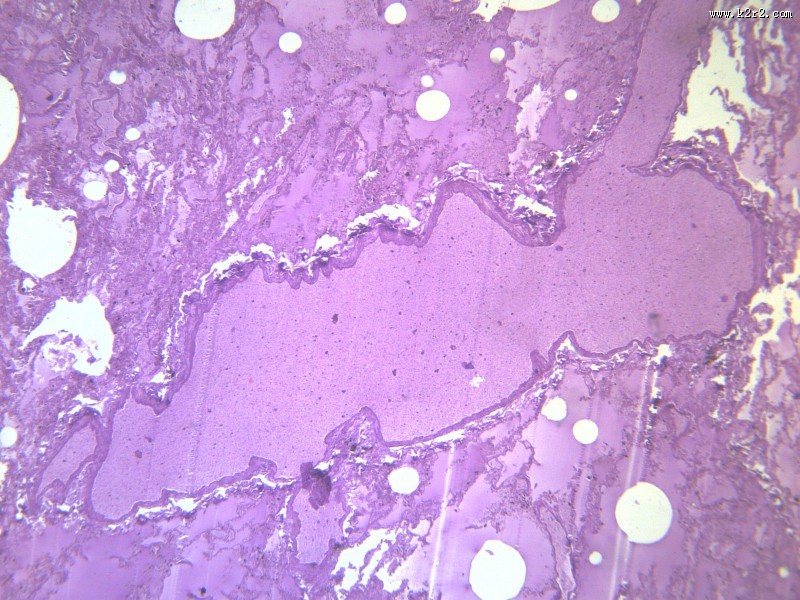

肺水肿(12张)

> 肺水肿 第4张

肺水肿 - 第4张

肺水肿

图集中 / 共有 12 张图片

肾小管水肿

医学

显微切片

pulmonaryedema